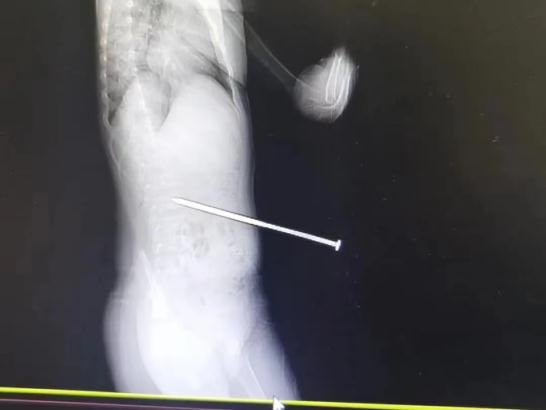

4月9日,杭州一名6岁男孩跟随父母在公园露营时,在草地上玩闹奔跑,不小心被固定帐篷的绳索绊倒,绳索连接的地钉一下子弹出地面,长约12厘米的地钉有6厘米随即扎进了他的腰部。所幸未伤及腹腔,男孩目前已经出院。

△图说:长约12厘米的地钉有6厘米扎进男孩腰部,所幸未伤及腹腔。图源:杭州市卫生健康委